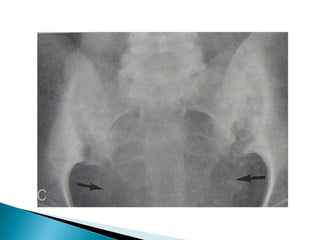

•   Subperiosteal cortical resorption of middle phalanges

•   Brown tumors

•   Renal calculi,Nephrocalcinosis

Osteoporosis • Subperiosteal cortical resorption of middle phalanges • Vertebral collapse • Brown tumors • Renal calculi,Nephrocalcinosis • Chondrocalcinosis